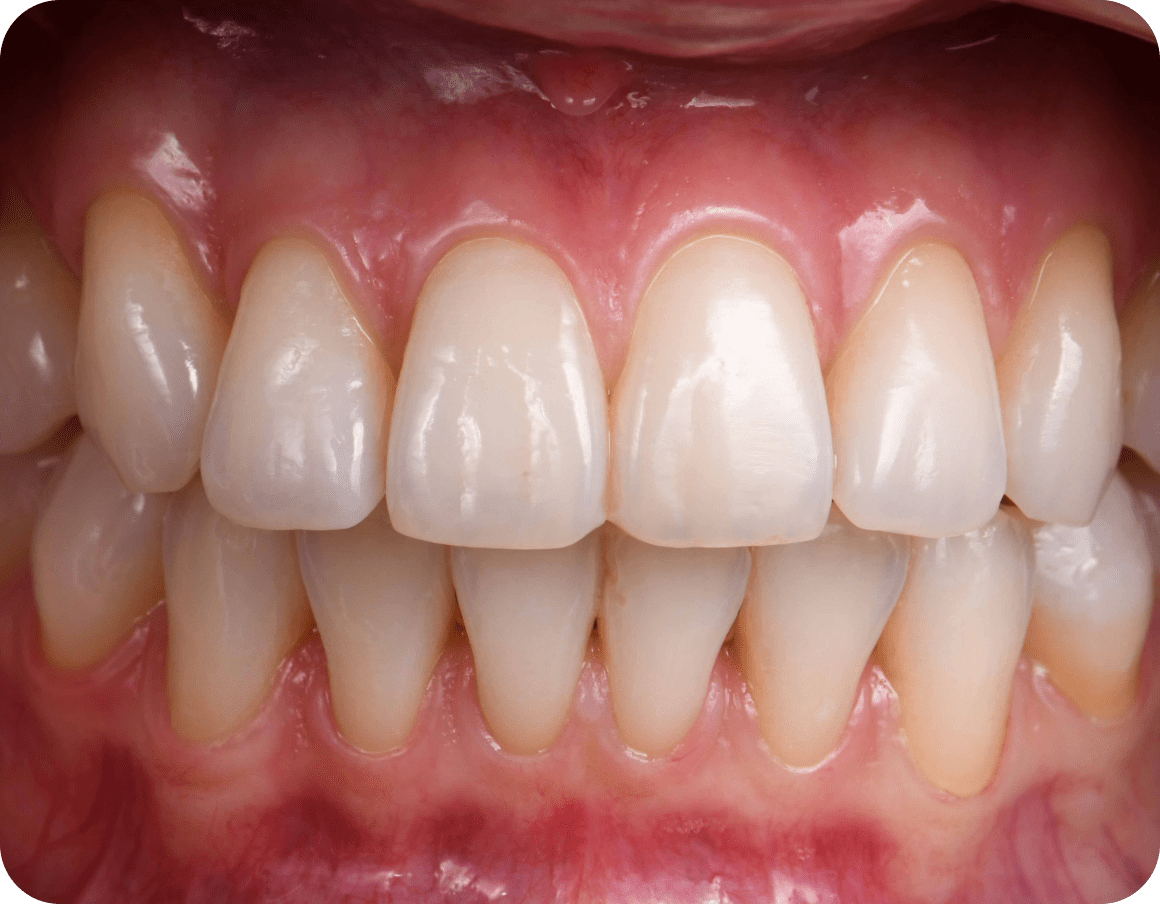

Финальный результат

В конце лечения мы убеждаемся, что зубы стали ровными, и пациент полностью удовлетворен результатом

Фиксируем положение зубов с помощью несъемного ретейнера или съемной прозрачной капой